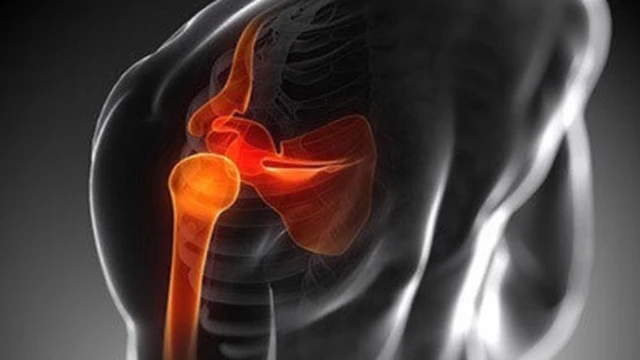

:format(webp)/dau_khop_xuong_quai_xanh_la_benh_gi_nguyen_nhan_va_cach_dieu_tri_1_2304c1108f.jpg)

Tình trạng đau khớp xương quai xanh (hay xương đòn) kéo dài sẽ gây ra nhiều bất tiện trong cuộc sống và có thể dẫn đến nhiều biến chứng xấu về sức khỏe. Vì vậy, việc hiểu rõ nguyên nhân và cách điều trị bệnh này là một việc vô cùng quan trọng.